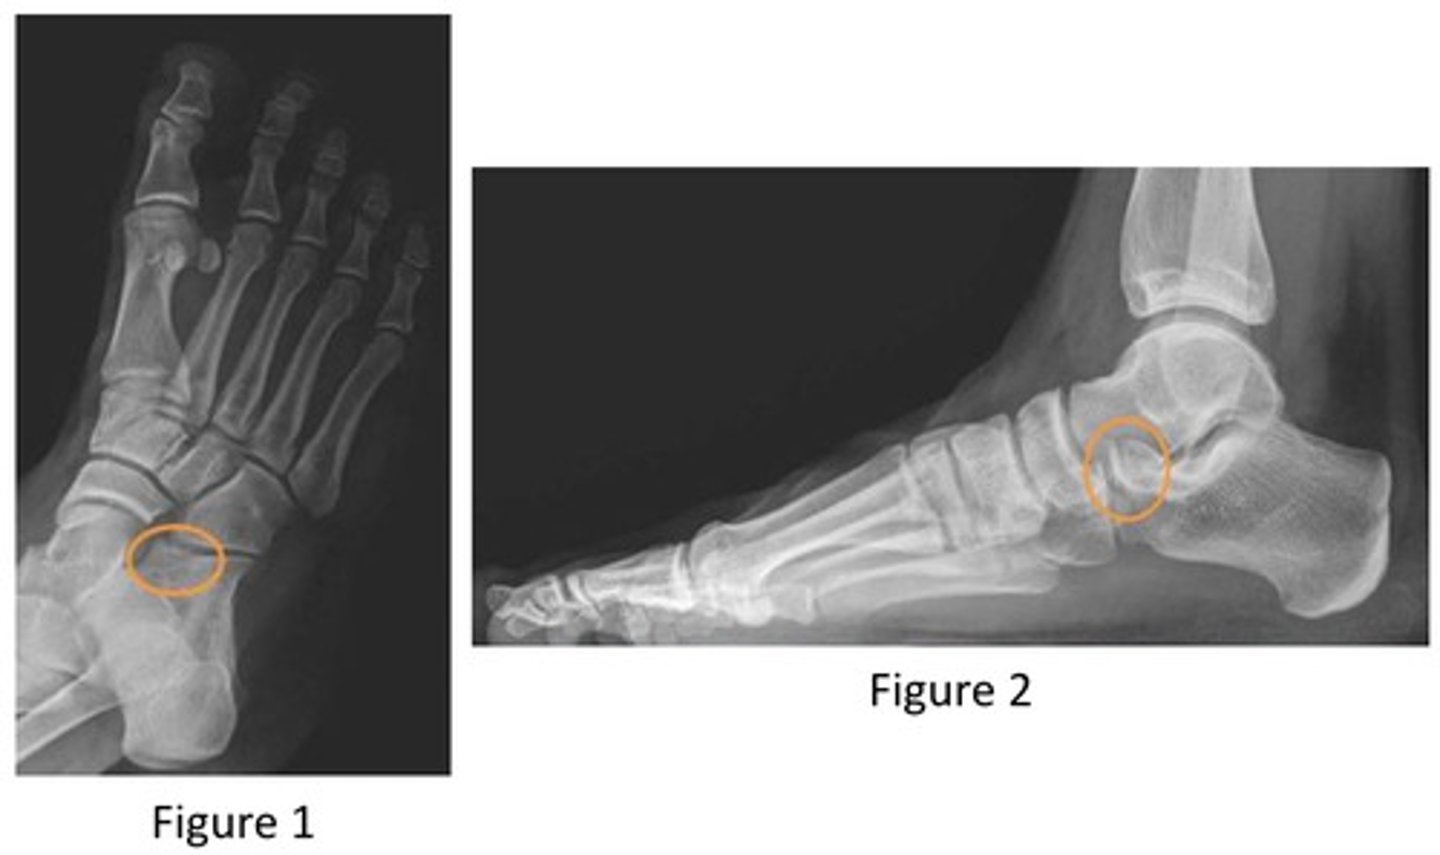

what do the orange circles in these radiographs indicate about the patient's injury to the anterior process of the calcaneus?

avulsion fracture

2 multiple choice options

after revealing a non-displaced fracture of the anterior process of the calcaneus, which of the following options will allow for the structure to heal?

controlled ankle movement (CAM) walking boot